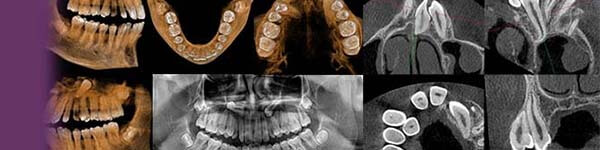

Discover Enhanced Imaging Solutions with Insightful Reports

At Insight Diagnostic, we understand that the journey of diagnosis is just the beginning of your practice. That's why we're committed to being your steadfast partner in elevating your dental expertise through cutting-edge imaging solutions. Allow us to introduce our "Insightful Reports" - a solution meticulously crafted to meet the unique needs of dentists like you who wish to enhance their dental practice without the hassle of mastering complex software or dedicating extensive time to it.

This specialized radiological report is derived from CBCT scans of the oral maxillofacial region. It offers an in-depth, localized 3D view of the patient's chief complaint or area of concern, using a combination of screenshots and video clips.

This specialized radiological Our CBCT-derived imaging reports are designed with a precise focus on addressing your diagnostic and treatment planning needs, all while being tailor-made to revolve around the patient's chief complaint. These reports are presented in easily digestible formats such as screenshots and video clips.